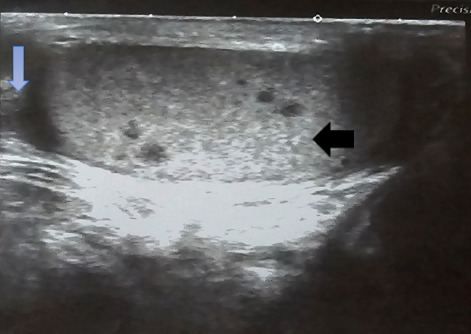

Extrapulmonary tuberculosis constitutes about 20% of all cases of tuberculosis. It involves organs other than the lungs, such as lymph nodes, the genitourinary tract, abdomen, skin, joints and bones, and meninges. Tuberculosis of the testis is a rare disease. The diagnosis of testicular tuberculosis could be confused with testicular cancer, sarcoidosis or metastases. Herein, we describe the ultrasonography of five patients with testicular tuberculosis. This case series highlights the importance of ultrasonography in the diagnosis of rare form of extra pulmonary tuberculosis.